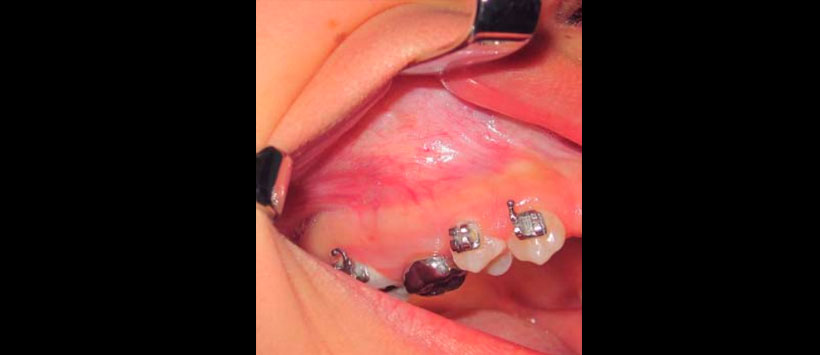

Paciente pediátrica de 12 años de edad referida a la Clínica de Cirugía Oral y Maxilofacial de la Universidad Veracruzana región Poza Rica-Tuxpan, con diagnóstico de quiste maxilar derecho, sin antecedentes relevantes en su historia médica para el padecimiento actual. Clínicamente presentaba aumento de volumen en región geniana derecha, intraoralmente en maxilar derecho, expansión cortical en región de premolares, tumefacción circunscrita, bien delimitada, indurada, coloración similar a la mucosa adyacente, presencia de segundo molar deciduo con una restauración con una corona acero-cromo (Figuras 1 a 3).